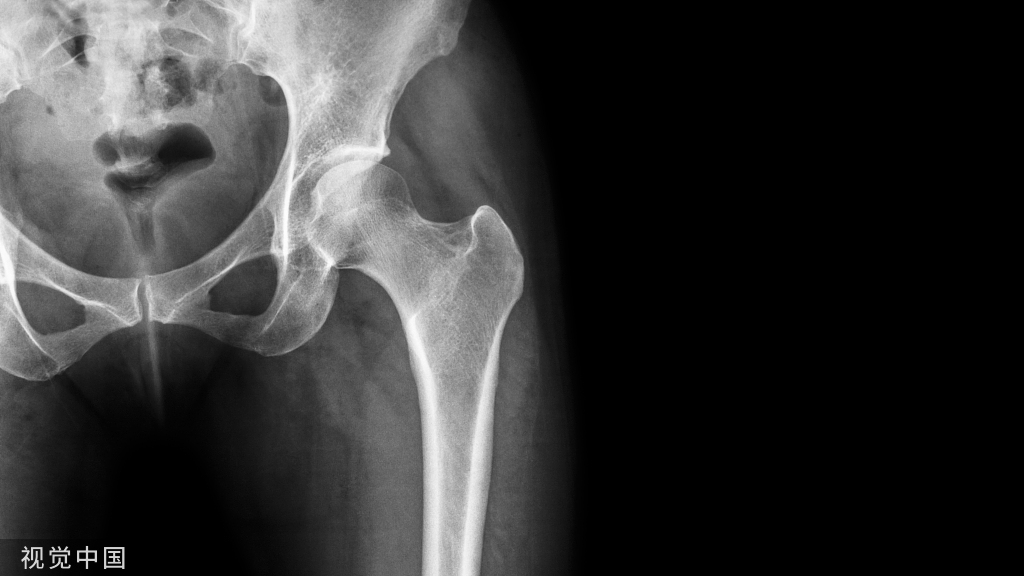

辅助检查:CBCT示38中位舌向阻生,部分骨埋伏,冠周包绕低密度影;37低位舌向阻生,完全骨埋伏,位于38近中下方,37舌侧骨板菲薄,毗邻下颌管及36远中根,下颌管轻度变形移位;36远中根轻度吸收;27牙冠位于28颊侧,28垂直位伴伸长(图1c)。

1a、1b:术前口内检查;1c术前CBCT影像